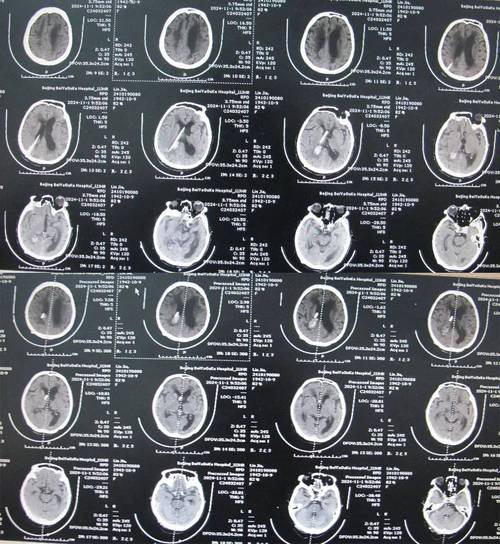

这是一个非常常见且重要的问题,答案是:头部CT在检查脑梗方面有局限性,但在特定情况下非常有价值。

为了完全理解这个问题,我们需要分情况讨论,并了解CT和MRI(磁共振成像)这两种主要影像学检查的区别。

头部CT能查出脑梗吗?—— 可以,但有“时间窗”限制

头部CT是急诊中最常用的快速脑部影像检查,它对于脑梗死的诊断能力,关键在于时间。

CT在脑梗诊断中的作用:

排除其他疾病(最重要的一点): 当患者出现类似中风的症状(如突发口角歪斜、肢体无力、言语不清等)时,医生首先需要排除其他可能致命的急症,特别是脑出血,CT对于脑出血的诊断非常敏感,能在几分钟内明确有无出血,如果CT显示有出血,治疗方案将完全不同,CT是急诊评估中风患者的“第一道防线”。

在特定时间窗内发现早期梗死迹象:

(图片来源网络,侵删)- 超早期(发病6小时内):在脑梗死的最初几个小时,CT检查通常是完全正常的,因为此时脑细胞刚刚开始缺血,脑组织的大小和密度还没有发生明显变化。

- 早期(发病6-24小时):随着缺血时间的延长,部分患者CT上可能会出现一些间接征象,经验丰富的放射科或临床医生可以发现:

- 脑沟变浅或消失:缺血区域的脑水肿导致脑回肿胀,使得脑沟(脑表面的沟壑)变浅。

- 豆状核模糊:基底节区的神经结构密度变得模糊不清,这是比较特异的早期征象。

- 大脑中动脉高密度征:提示该动脉内有血栓形成,是血管堵塞的直接证据。

- 亚急性/慢性期(发病24小时后):发病24小时至数周后,梗死区域的脑组织因为缺血坏死,会密度明显降低(变黑),并且会出现脑组织萎缩,这时,CT诊断脑梗死就变得非常容易和明确了。

CT在脑梗诊断中的局限性:

- 对超早期脑梗死不敏感:这是CT最大的缺点,如果患者在发病6小时内做CT,结果正常,绝对不能排除脑梗死,此时如果需要更早的诊断,就必须做MRI。

- 对小梗死灶不敏感:对于发生在脑干、小脑或皮层的小梗死灶,CT很难发现,容易漏诊。